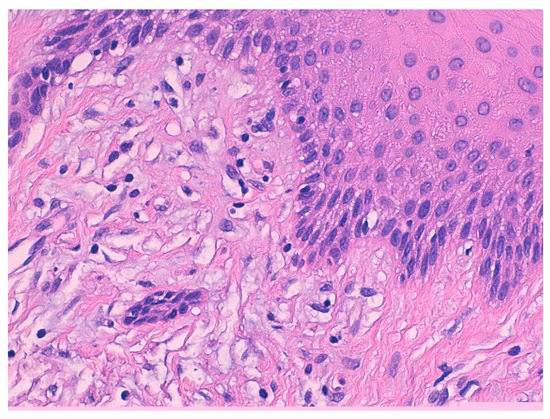

3.1. Histological Characteristics